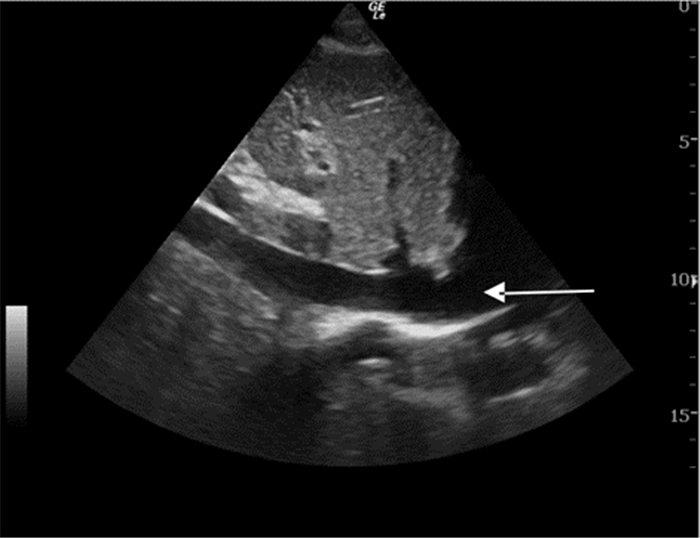

超声检查IVC内径及其随呼吸的变异率不但能提供患者容量状态的信息,有时还能评估液体反应性(图 19、20)。ASE(美国心超协会)指南的建议:用力吸气时,IVC直径≤2.1 cm伴随呼吸变异率>50%,对应于中心静脉压(CVP)值3 mmHg(0~5 mmHg,1 mmHg=0.133 kPa),IVC直径>2.1 cm伴随呼吸变异率<50%,对应的CVP值为15 mmHg(10~20 mmHg);如IVC直径≤2.1 cm伴随呼吸变异率<50%或IVC直径>2.1 cm伴随呼吸变异率>50%,提示对应的CVP值可能为8 mmHg(5~10 mmHg),此时应考虑采用其他指标来估测CVP[1]。其他文献报道数值略有不同,平静呼吸时,IVC直径≤2 cm伴随呼吸变异率>50%,对应于CVP值≤10 mmHg,可见于低血容量和分布性休克患者;IVC直径>2 cm伴随呼吸变异率<50%,对应的CVP值大于10 mmHg,可见于心源性和梗阻性休克患者[2]。

| 图 19 IVC长轴切面 |

但IVC的超声成像有时比较困难,特别是肥胖、腹胀和肠胀气明显的患者;而且IVC大小还受机械通气患者呼气末正压(PEEP)的影响,用来估计CVP有一定的缺陷[3]。在完全控制通气模式下(无自主呼吸触发)时,吸气相IVC扩张超过12%~18%,可较好的预测容量反应性。IVC管径随着PEEP水平的增加而升高,呼吸变异率随PEEP的增加而变小,但目前PEEP对IVC容量评估的影响尚无定论,有待进一步临床研究。